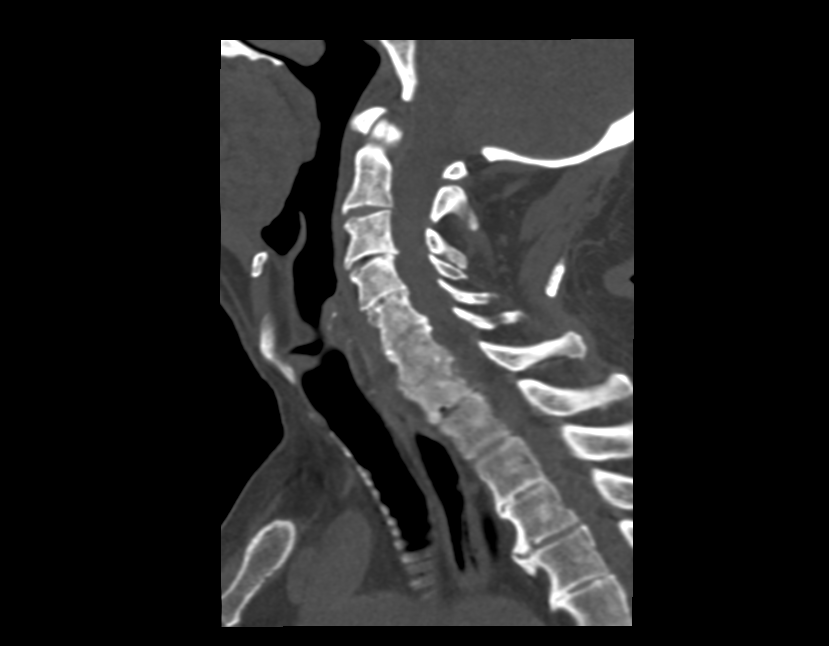

В прошлых статьях мы обсуждали принципы и достоинства КТ и МРТ исследований, но здесь важно отметить, что благодаря как раз таки своим принципам работы и особенностям аппаратного обеспечения, каждый из этих методов исследований в контексте различных заболеваний могут выступать как “золотым” стандартом, так и скрининговым (обзорным) методом. К примеру, для визуализации легких “золотым” стандартом является КТ, так как жидкости в такой нежной структуре достаточно мало, соответственно мало атомов водорода для МРТ-визуализации.